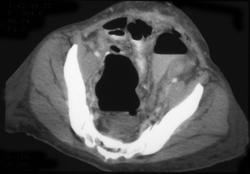

Diagnosis

Ischemic Colitis